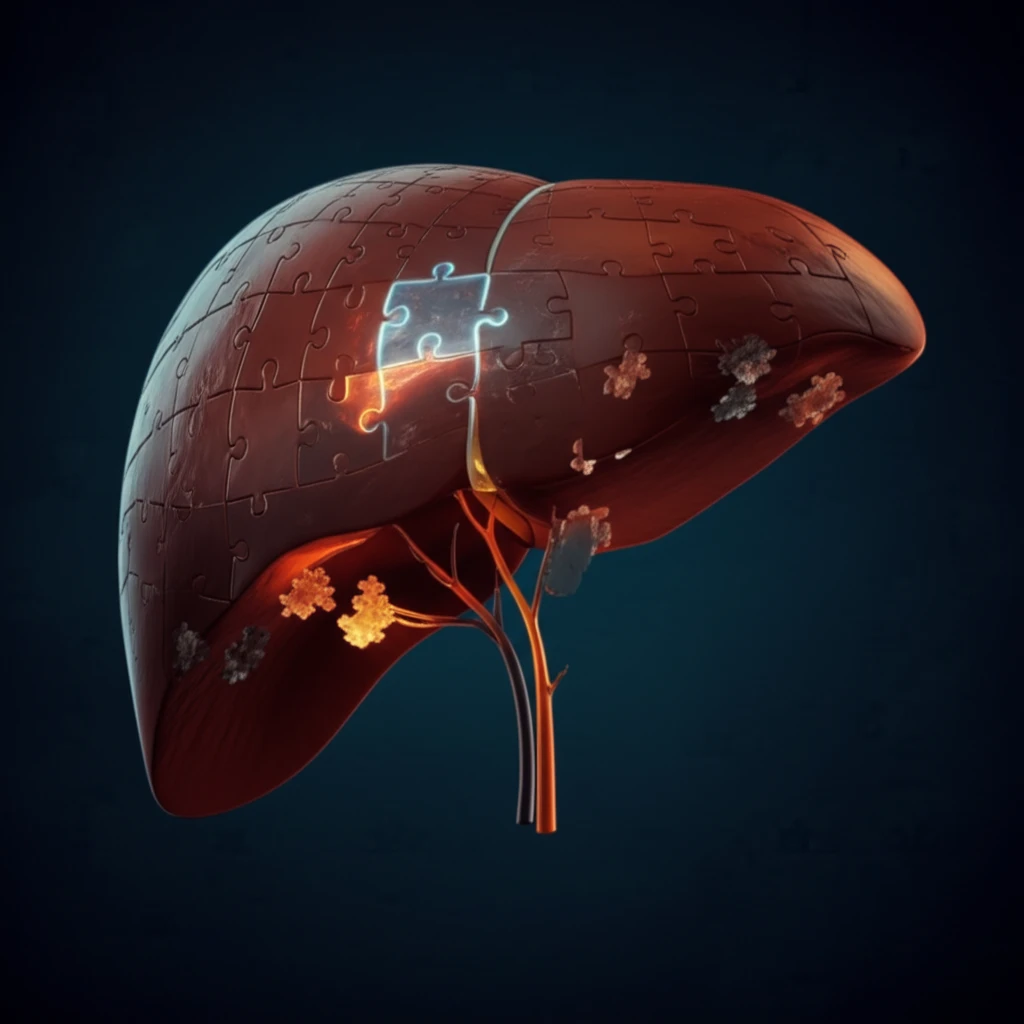

However, even the most sophisticated imaging has its limitations. Primary hepatic lymphoma (PHL), a rare cancer that starts in the liver, can sometimes mimic other liver conditions on imaging, making accurate diagnosis a challenge. This is where a liver biopsy becomes essential.

Primary hepatic lymphoma (PHL) is an exceedingly rare cancer, often overshadowed by more prevalent liver conditions. Its subtle presentation can easily lead to misdiagnosis, making it a diagnostic puzzle for clinicians.